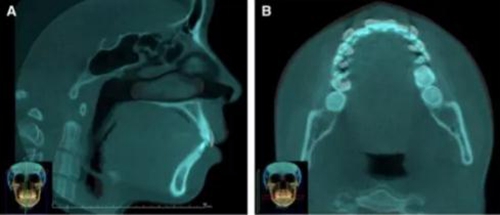

頭側(cè)分析提示為骨性安氏II類(lèi)(ANB,8.4°;Wits,3.6mm),高角(SN-MP,44.9°),上頜切牙略舌傾(U1-SN,96.2°),下頜切牙略舌傾(IMPA,88。3°)(圖2;表)